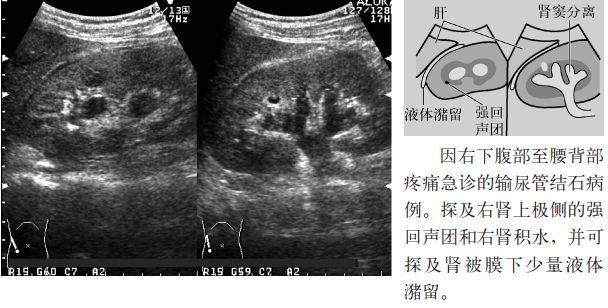

临床必备肾结石输尿管结石超声表现一览